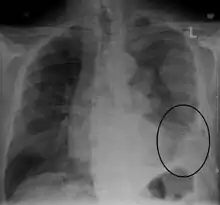

Diagnosing mesothelioma is often difficult because the symptoms are similar to those of a number of other conditions. Diagnosis begins with a review of the patient's medical history. A history of exposure to asbestos may increase clinical suspicion for mesothelioma. A physical examination is performed, followed by chest X-ray and often lung function tests. The X-ray may reveal pleural thickening commonly seen after asbestos exposure and increases suspicion of mesothelioma.[15] A CT (or CAT) scan or an MRI is usually performed. If a large amount of fluid is present, abnormal cells may be detected by cytopathology if this fluid is aspirated with a syringe.[11] For pleural fluid, this is done by thoracentesis or tube thoracostomy (chest tube); for ascites, with paracentesis or ascitic drain; and for pericardial effusion with pericardiocentesis. While absence of malignant cells on cytology does not completely exclude mesothelioma, it makes it much more unlikely, especially if an alternative diagnosis can be made (e.g., tuberculosis, heart failure). However, with primary pericardial mesothelioma, pericardial fluid may not contain malignant cells and a tissue biopsy is more useful in diagnosis.[11] Using conventional cytology diagnosis of malignant mesothelioma is difficult, but immunohistochemistry has greatly enhanced the accuracy of cytology.